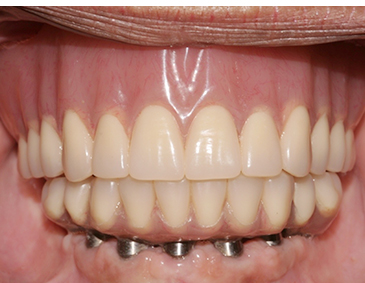

Fully edentulous clinical cases